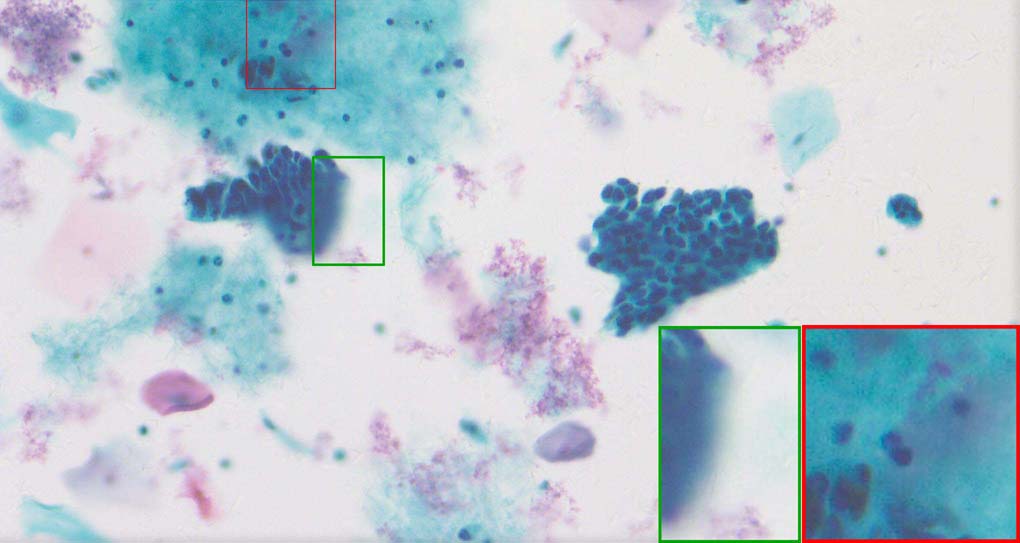

To demonstrate the effectiveness and efficiency of the proposed image fusion method , we conduct a set of comparative experiments on three image datasets. The first is composed by 8 pairs of multi-modal medical images and the second one contains 15 pairs of multi-focus gray or color natural images. These two datasets are often used in many related papers and some examples are shown in Figure 3(a) and Figure 3(b). The third one is a new multi-focus cervical cell image dataset collected by ourselves, which consists of 15 groups of color images and each group contains a series of multi-focus cervix cell images with size of or , etc. Some source examples are shown in Figure 3(c). Our source code implemented in C++ along with the new multi-focus cervical cell image dataset is available online.

Figure 9, Figure 10 and Figure 11 show the comparative fused results of the multi-focus cell images shown in Figure 3(c). For clarity, we also present a closeup view in the right-bottom of each sub-picture in Figure 9 and Figure 10. As shown in the close-up views of Figure 9, the fused images based on DSIFT, IM, MWGF and BF methods are extremely blurred in the boundary and fail to keep the details of cell nucleus. Furthermore, the DTCWT and NSCT based methods produce halo artifacts in the fused images, while GFF and CNN based methods fail to preserve the small cell nucleus. LP-SR based method nearly works fine which keeps the most of the details of the small size cells, but the integrity of the clustered large size cells is damaged. Fortunately, in our proposed method, the integrity of the clustered large size cells is preserved and most of the isolated small size cells are maintained from the original images, which demonstrates the best visual quality.

Similarly, as shown in the close-up views of Figure 10, the fused images from DSIFT, IM, MWGF and BF are blurred and lose some nucleus details, while the results from DTCWT, GFF, CNN and NSCT produce halo artifacts. LP-SR based method can keep details well but also produces halo artifacts and other noise. Our method can preserve the focused areas of different source images well without introducing any artifacts. For the example illustrated in Figure 11, the fused images generated by DSIFT, DTCWT, IM and NSCT all fail to preserve the focused areas of different source images and result in extremely blurred images. The GFF, CNN, MWGF and BF based method introduces a lot of color distortion of the nucleus regions and the obvious halo artifact. The result of LP-SR based method is close to the one of our method but introduces some odd color distortion. Again, our method produces fused image which can preserve the focused areas of different source images well without introducing any artifacts.